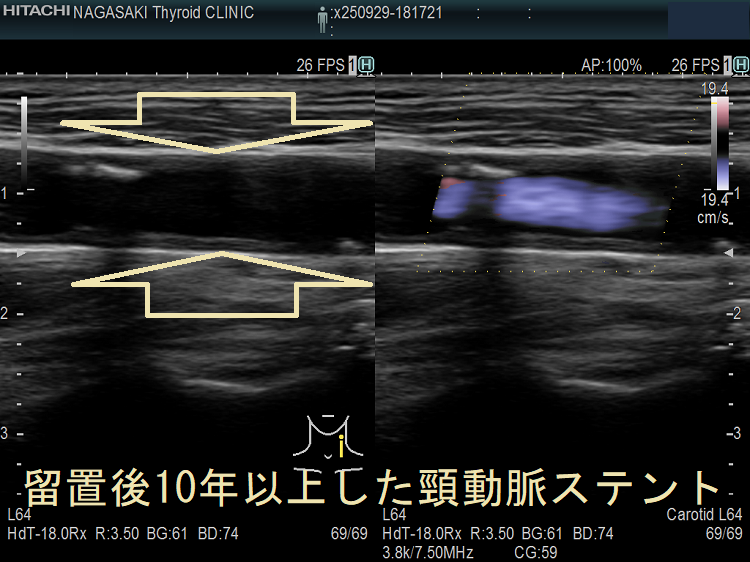

甲状腺機能低下症/潜在性甲状腺機能低下症/橋本病、糖尿病などでは動脈硬化が進み、頚動脈プラークにできた血栓が脳へ流れて脳梗塞。最悪、頚動脈自体の閉塞も。血管エコーでプラークを探す。動脈硬化血管は硬くもろく、大動脈では血圧に負けて大動脈瘤に。頸動脈閉塞度70%以上でカテーテル手術、ステント留置。時間が経つとステント上に新たなプラーク形成。内頸動脈ステント留置時、ガイドワイヤーで外頸動脈枝の上甲状腺動脈穿孔おこした報告あり。コレステロール/脂質塞栓が、網膜動脈を完全/不完全閉塞すると黄色斑(ホレンホースト斑)が生じる。

頸動脈ステントを留置した患者の甲状腺 超音波(エコー)画像;写真の頸動脈ステントを留置した患者は、甲状腺機能低下症/橋本病により動脈硬化が進行していました。(甲状腺と動脈硬化)

脳卒中治療ガイドライン 2021〔改訂2025〕では、軽度~中等度の頸動脈狭窄に頸動脈ステント留置や手術によるプラーク除去(頸動脈内膜剥離術)を行わないよう勧めています。

高度狭窄か脳梗塞を伴う中等度以上狭窄に対し、頸動脈ステント留置よりも手術によるプラーク除去(頸動脈内膜剥離術:CEA)を推奨しています。手術不能例には頸動脈ステント留置(CAS)。